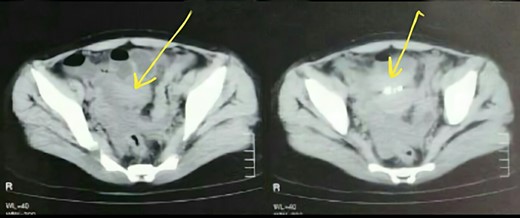

A 23-year-old woman presented to hospital complaining of chronic constipation that had started 2 month earlier. It was accompanied by colic abdominal pain and recurrent vomiting. Her general condition, appetite, urination, sleep and vital signs were all normal. As a history, she was admitted in a hospital previously with bowel obstruction due to sigmoid colon volvulus, but she was discharged after 2 days without any intervention. On physical examination, there was hypogastric pain without tenderness and visceral movements were slightly increased in the hypogastric and periumbilical regions. On radiology investigations, chest X-ray and echography of abdomen were all normal. CT scan showed multi-density formations in the left iliac region with a small amount of pelvic fluid (Fig. 1). The Barium Enema showed sigmoid colon elongation, without filling defects.

We performed exploratory laparoscopy and found a mass measured (2 × 3 cm) on the left pelvic between the bladder and the uterus, adjacent to the left ovary. A 100-ml serous fluid was found in the pelvis and was aspirated. Furthermore, we noticed formations on the left iliac region adjacent to the parietal peritoneum. We resected the mass and the other formations and sent them to pathology that revealed an aggregation of lipid laden macrophages (foamy cells) (Fig. 2) that is infiltrated by lymphocytes and neutrophils and blood vessels congestion (Fig. 3). These findings suggested Peritoneal Xanthogranuloma with massive necrosis and no ovarian parenchyma. The aspirated fluid was bloody and inflammatory with no signs of malignancy.